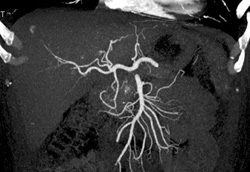

Cholangiocarcinoma